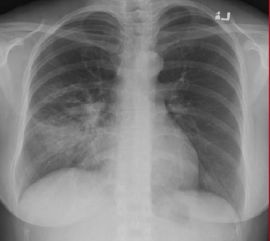

《塵肺病診斷中常用的三種方法:X胸片、CT檢查、核磁共振檢查》中我們和大家分享了X射線檢查是塵肺病診斷中最主要、最常用的方法。

因而質(zhì)量?jī)?yōu)等的X射線胸片對(duì)于塵肺病的診斷有這極為重要的意義,這就要求在實(shí)際工作中工作人員必須有高度的責(zé)任感,還要不斷的提高自己的技術(shù)水平。那么在塵肺病診斷中拍X射線胸片要注意什么呢?下面我們就為大家做一個(gè)詳細(xì)的解答,一起來(lái)看看吧無(wú)論有什么先進(jìn)的設(shè)備條件,沒(méi)有認(rèn)真負(fù)責(zé)的工作態(tài)度,不嚴(yán)格執(zhí)行操作規(guī)范,就不可能拍攝出質(zhì)量?jī)?yōu)等的胸片。

在具體的工作中,塵肺病拍X射線胸片要注意以下四點(diǎn):1、基礎(chǔ)設(shè)備要配套。X射線機(jī)的各項(xiàng)技術(shù)參數(shù)必須符合高仟伏攝影的技術(shù)要求,對(duì)設(shè)備要經(jīng)常進(jìn)行維修,保證其正常工作狀態(tài)。

2、攝影條件要定好。攝片技術(shù)條件是保證胸片質(zhì)量的最重要的因素。

攝影條件表綜合包含了X射線和各種配套設(shè)備的性能、暗室條件、膠片感光性能、受檢者的胸厚等因素。這對(duì)于塵肺病、矽肺病的診斷是基礎(chǔ)性的一環(huán)。